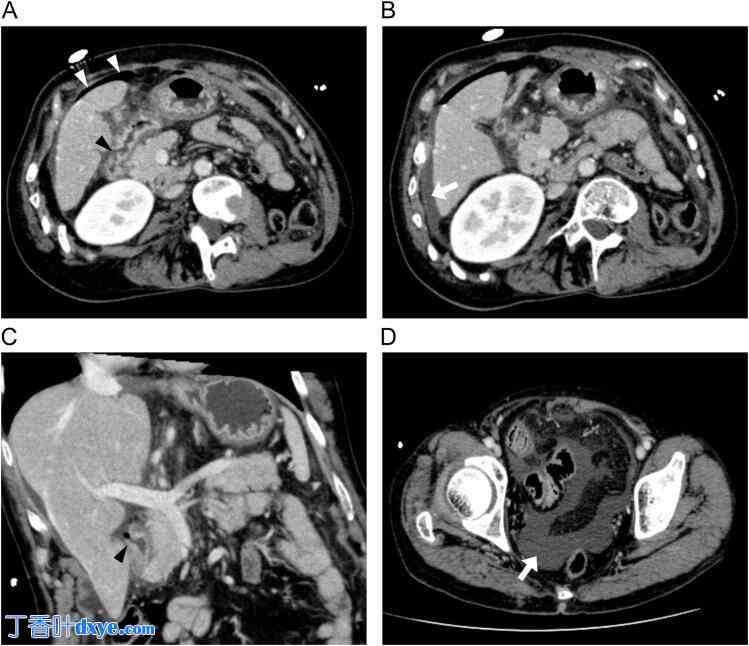

腹部增强CT扫描显示十二指肠壁不连续,肝脏表面有游离气体,并有少量腹水(图2A-C),符合十二指肠球部穿孔的诊断。此外,道格拉斯窝可见中量腹水(图2D)。基于以上发现,患者接受了急诊腹腔镜手术,确诊为十二指肠溃疡穿孔。

图 2.

腹部增强 CT 显示十二指肠壁不连续(黑色箭头),肝脏表面游离气体(白色箭头),少量腹水(白色箭头)(图 A、B、C)。

道格拉斯窝内可见中等量腹水(白色箭头)(图 D)。